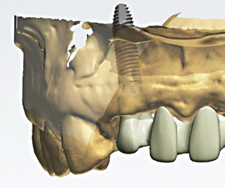

Além dos implantes, as próteses também passaram por reformulações. O Neoshape é o sistema desenvolvido pela Neodent que possibilita ao dentista obter próteses personalizadas com uma resolução estética naturalmente perfeita. Antes do advento dessa tecnologia só era possível fazer a prótese usando metal revestido com cerâmica, um processo manual que, em algumas situações, dava pouca naturalidade ao dente implantado.

A nova tecnologia é toda digital. Os especialistas conseguem planejar na tela do computador de forma tridimensional todos os detalhes estéticos e funcionais da prótese.

Além disso, existe a possibilidade da peça ser confeccionada sem o uso das ligas metálicas utilizando em seu lugar a zircônia. Ela é revestida com uma cerâmica vítrea de di-silicato de lítio que deixa a prótese similar a um dente real.